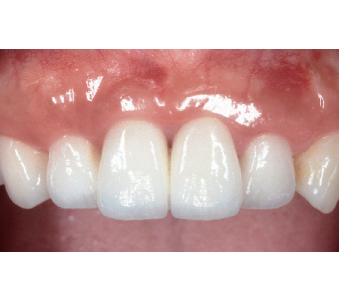

결과로 증명합니다.

국제모아치과의

실제 임상 증례